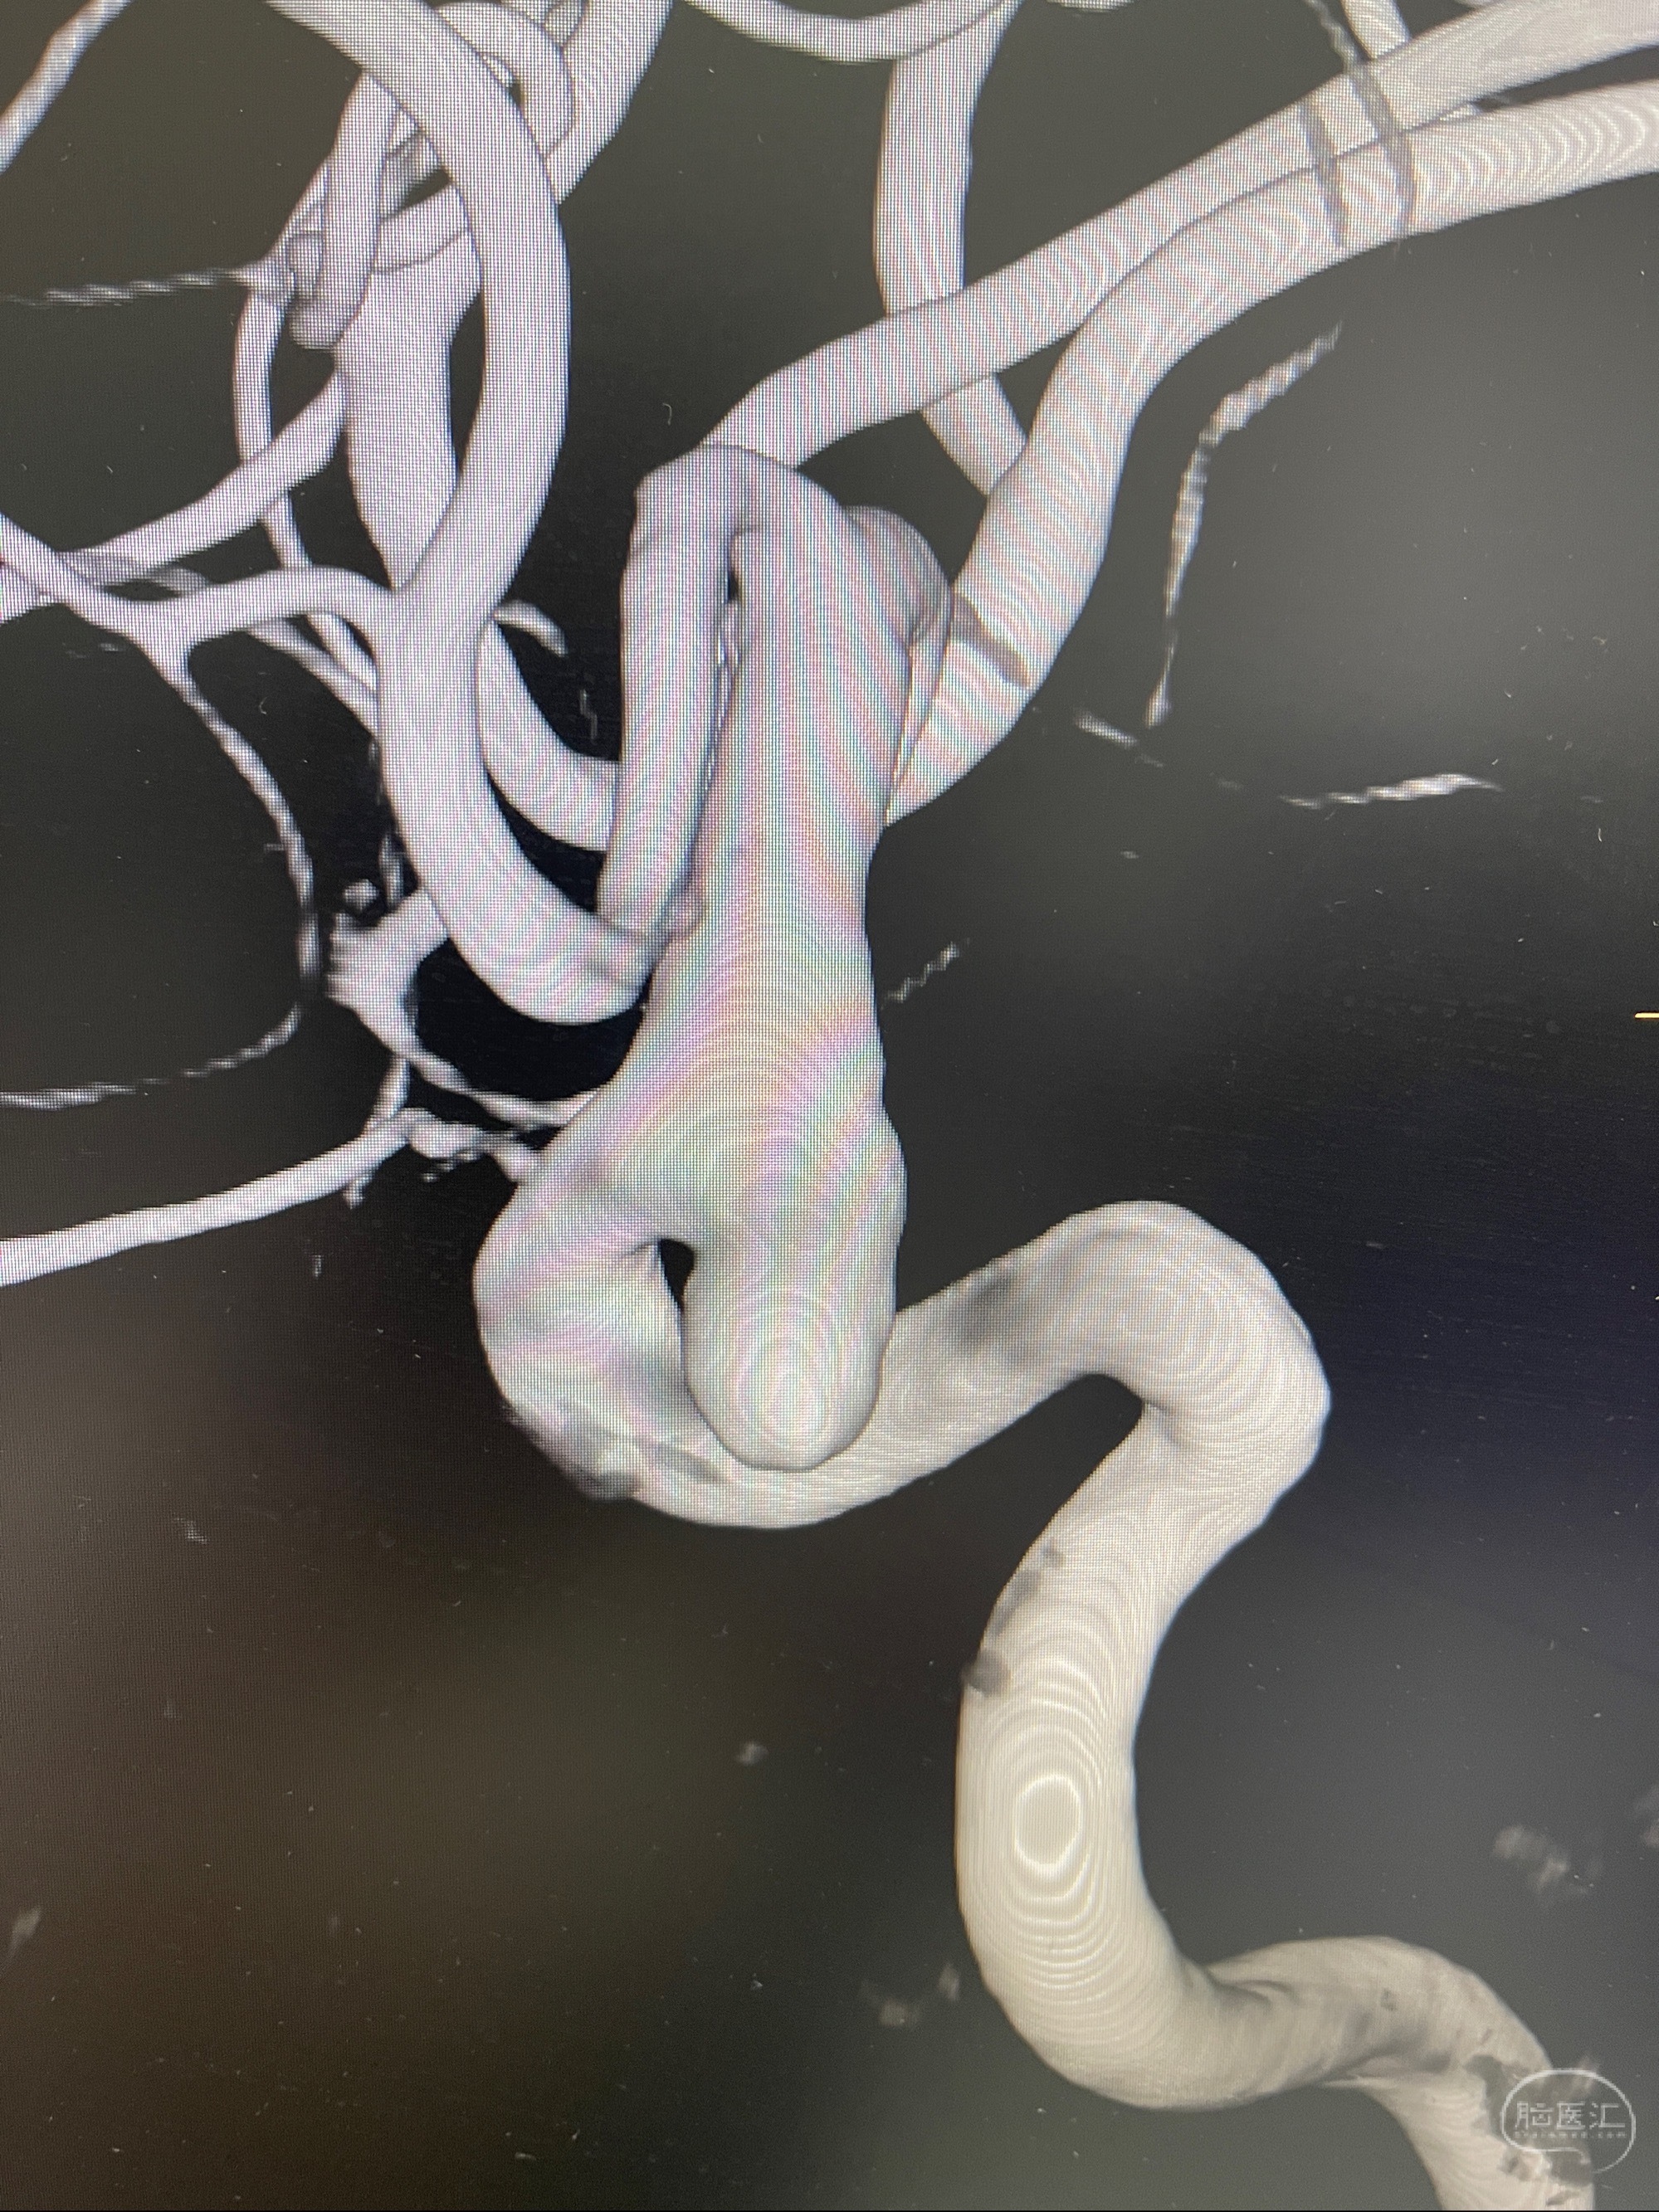

1.右侧颈内动脉眼动脉段动脉瘤

2023-07-27全脑血管造影:双侧颈内动脉眼动脉段动脉瘤,右侧较大

2023-08-01全麻下行双侧颈眼动脉瘤支架辅助栓塞

- pipeling4.5-20mm

- pipeline 4.0-20mm

手术顺利,麻醉苏醒佳,遵嘱动作